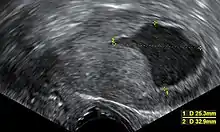

ازداد استخدام الموجات فوق الصوتية عبر المهبل لفحص سمك بطانة الرحم في النساء اللاتي يعانين من نزيف بعد فترة اليأس في الولايت المتحدة مما يساعد على تشخيص سرطان بطانة الرحم[39]، بينما في المملكة المتحدة يتم استخدام كل من الخزعة البطانية الرحمية والموجات فوق الصوتية عبر المهبل بالاقتران مما يُشكِّل مستوى الرعاية لتشخيص سرطان بطانة الرحم[15]، ويُمكن أن يساعد تجانس الأنسجة المرئية في الموجات فوق الصوتية عبر المهبل في تحديد ما إذا كان سمك بطانة الرحم سرطانيًا، وتكون نتائج الموجات فوق الصوتية وحدها غير حاسمة في حالات سرطان بطانة الرحم؛ لذلك يتم استخدام وسيلة أخرى مثل الخزعة البطانية الرحمية بالاقتران معها، بينما تكون دراسات التصوير الأخرى ذات استخدام محدود، فتُستخدم الآشعة المقطعية في التصوير قبل العمليات الجراحية للأورام التي تظهر بصورة متقدمة في الاختبارات البدنية أو لديها أنواع فرعية عالية الخطورة (معدل مرتفع من الانبثاث)[40]، كما يمكن استخدام الآشعة المقطعية أيضًا في فحص الأمراض التي تقع خارج الحوض[15]، ويُستخدم التصوير بالرنين المغناطيسي في تحديد إذا ما انتشر السرطان إلى عنق الرحم أو إذا كان عبارة عن سرطانة غدية داخل عنق الرحم[40]، أيضًا يتم استخدام التصوير بالرنين المغناطيسي لفحص العقد الليمفاوية المُجاورة.[15]